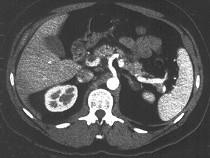

问题 男性,40岁,半年前因双下肢麻木、发凉、疼痛于外院诊断血栓闭塞性脉管炎,近1周腹痛、腹胀,以中下腹为著,呈阵发性加剧就诊,行CT增强扫描,如图所示 ( )

选项 A.胰头部略膨隆,内部密度不均。 B.门静脉及肠系膜肠系膜上静脉增宽。 C.门静脉及肠系膜静脉内见条形充盈缺损。 D.考虑为胰头癌。 E.考虑为门静脉及肠系膜内血栓形成。

答案 ABCE